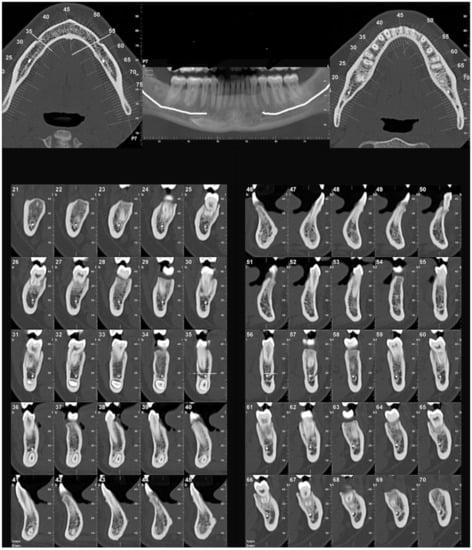

3. Results